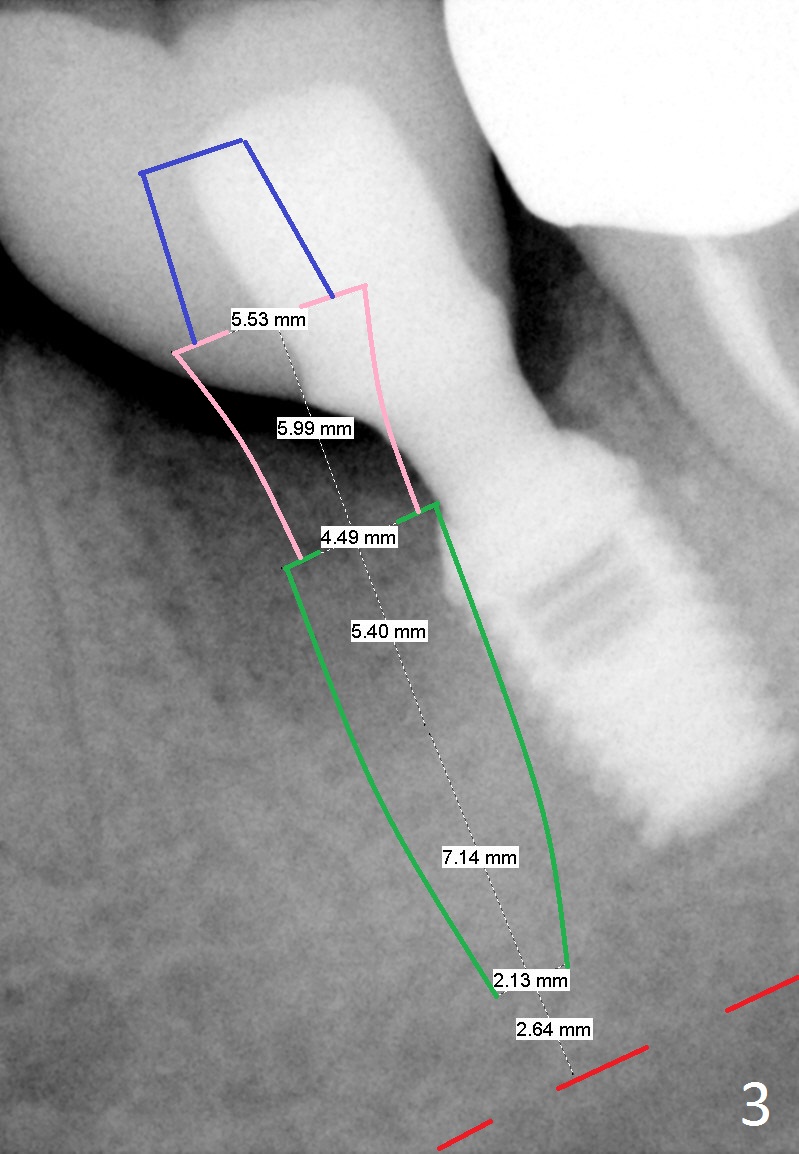

Etiology of Periimplantitis A 42-year-old woman presented to clinic 11 years ago with history of extraction of the tooth #19 two months earlier (Fig.1). Two months later, a 5x8 mm Bicon implant was placed (Fig.2). Integrated Abutment Crown was delivered 2 years later (Fig.3) with persistent radiolucency in the mesial socket. The tooth #18 was extracted with socket preservation 7 years ago. Recently she returned with chief complaint of chewing pain in the lower left for a while. The buccal gingiva of #19 is erythematous, edematous and tender (Fig.4). There are healing abutment at #29 and implant crown at #30. Periimplantitis at #19 is most likely due to buccodistal placement. When it is removed (Clindamycin), a smaller IBS or SM implant will be placed immediately and mesiolingually (Fig.3). For better wound protection with periodontal dressing or provisional, an implant will be placed at #18 at the same appointment. Draw blood for PRF if the vein is large enough. Surgical stents have been in cold sterilant. Return to Lower Molar Immediate Implant, Prevent Molar Periimplantitis (Protocols, Table), Course 1 2 Fig.1 Remedy Xin Wei, DDS, PhD, MS 1st edition 06/16/2017, last revision 06/26/2020 |